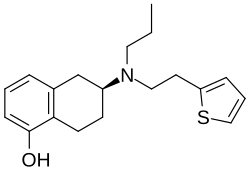

| Formula | C19H25NOS |

| Molar mass | 315.48 g·mol−1 |